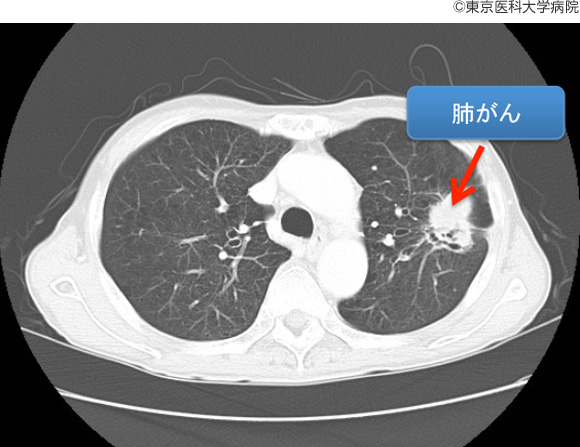

肺がんは、初期段階で診断することが難しい重篤な疾患です。しかし、研究者たちは肺がんの早期発見に役立つ、より効果的な診断ツールの開発に取り組んでいます。早期発見は治療をより効果的にするのに役立ちます。

低線量 CT スキャンでは、従来の CT スキャンよりも被曝する放射線量が少なくなります。また、以前は肺がんのスクリーニングに使用されていた胸部 X 線検査よりも正確です。肺がん検診について詳しくはこちらをご覧ください。

肺がんのリスクがあり、肺がんに関連する症状がある場合は、医師の診察を受けてください。低線量 CT スキャンは、過去に使用されていた診断ツールよりも早期がんの検出に効果的です。